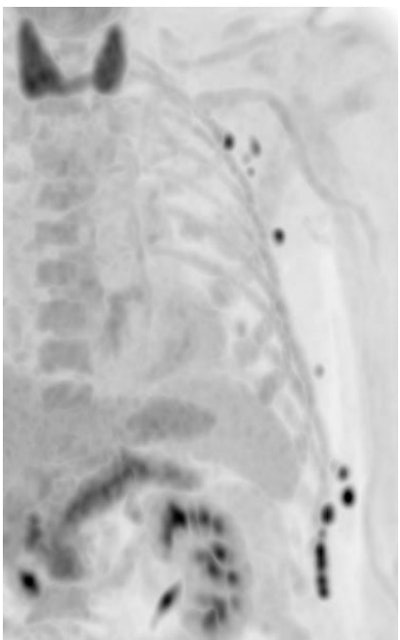

Long axial field-of-view (LAFOV) technology is also interesting in children, as it enables the reduction of dose drastically, said Rominger, who shared the example of an eight-year-old child with Morbus Hodgkin disease and cervical, bone, and splenic involvement.

"The child underwent chemotherapy and we reduced the dose down to 14 MBq, so 0.5 MBq per kilo. We obtained very nice corresponding reconstruction and preserved image quality," he said.

LAFOV PET/CT could thus be a game-changing option for children, he believes. "You can either inject a more or less regular dose and then do ultrafast acquisition, and thus avoid anesthesia in a certain number of children. Or you can inject an ultralow dose and do a regular scan and avoid as much radiation burden as possible," he said.

In a recent case report, Dutch researchers imaged a ten-week-old infant with LAFOV PET/CT, using 12 MBq in three minutes, thus avoiding sedation. 'That's a very low dose. It's a very nice development and offers new opportunities in children," he said.